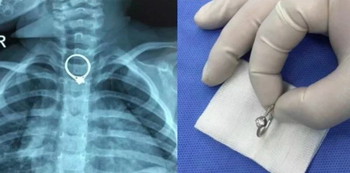

Melalui prosedur operasi yang berlangsung selama 30 menit, cincin berdiameter 2,35 sentimeter itu berhasil dikeluarkan dari tubuh anak. Untungnya kesigapan sang ibu langsung membawa anaknya ke rumah sakit dapat mencegah terjadinya dampak buruk lebih lanjut.

Dokter yang memimpin operasi ini mengatakan, kasus anak menelan benda asing bukan baru pertamakali ini terjadi. Kasus ini sering terjadi pada balita, yang menelan benda berukuran kecil dan menyebabkan risiko tersedak.

Oleh sebab itu, dokter menghimbau para orangtua untuk ekstra waspada, dan tidak membiarkan anak bermain dengan benda-benda kecil yang berisiko tertelan anak.

anak menelan benda asing 2

Anak menelan benda asing adalah kasus yang sering terjadi, orangtua harus ekstra waspada.